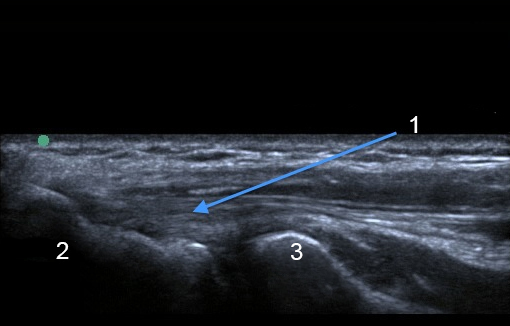

Image : Coude : Tendon extenseur commun

Tendon extenseur commun

Épicondyle latéral

Tête radiale